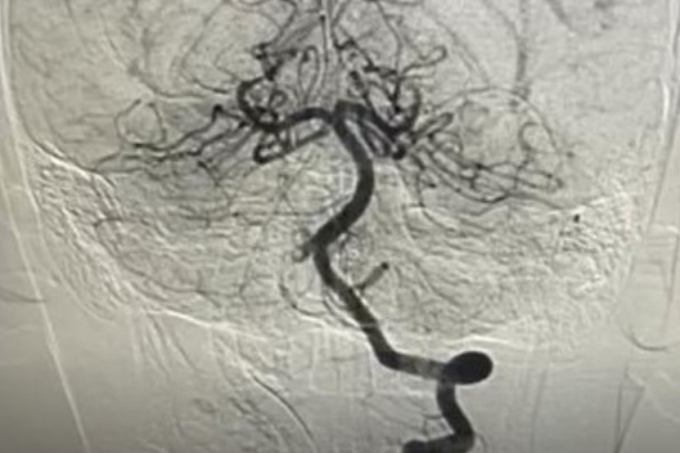

Các bác sĩ nhanh chóng hội chẩn liên khoa, chỉ định chụp mạch máu não và can thiệp nội mạch cấp cứu. BS.CK2 Trần Công Bảo Phụng và êkíp đã tiêu sợi huyết tại chỗ kết hợp hút huyết khối, tái thông hoàn toàn mạch máu não. Sau một tuần điều trị, bệnh nhi tỉnh táo, vận động phục hồi gần như bình thường, không ghi nhận di chứng thần kinh.

Bác sĩ can thiệp tái thông mạch máu cho bệnh nhi. Ảnh: Bệnh viện cung cấp